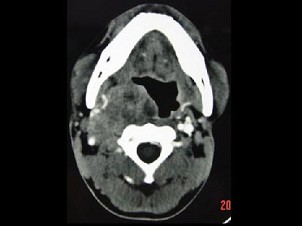

男,41岁,右侧咽部不适两年余,有异物感,声音嘶哑,CT如图所示,最可能诊断为 ( ) EBH-00941.jpg EBH-00942.jpg EBH-00943.jpg EBH-00944.jpg

题型: 单选题 分类: 耳鼻喉(头颈外科)学

• A.咽旁转移癌

• B.咽旁神经鞘膜瘤

• C.颈动脉体瘤

• D.咽旁淋巴瘤

• E.小唾液腺瘤